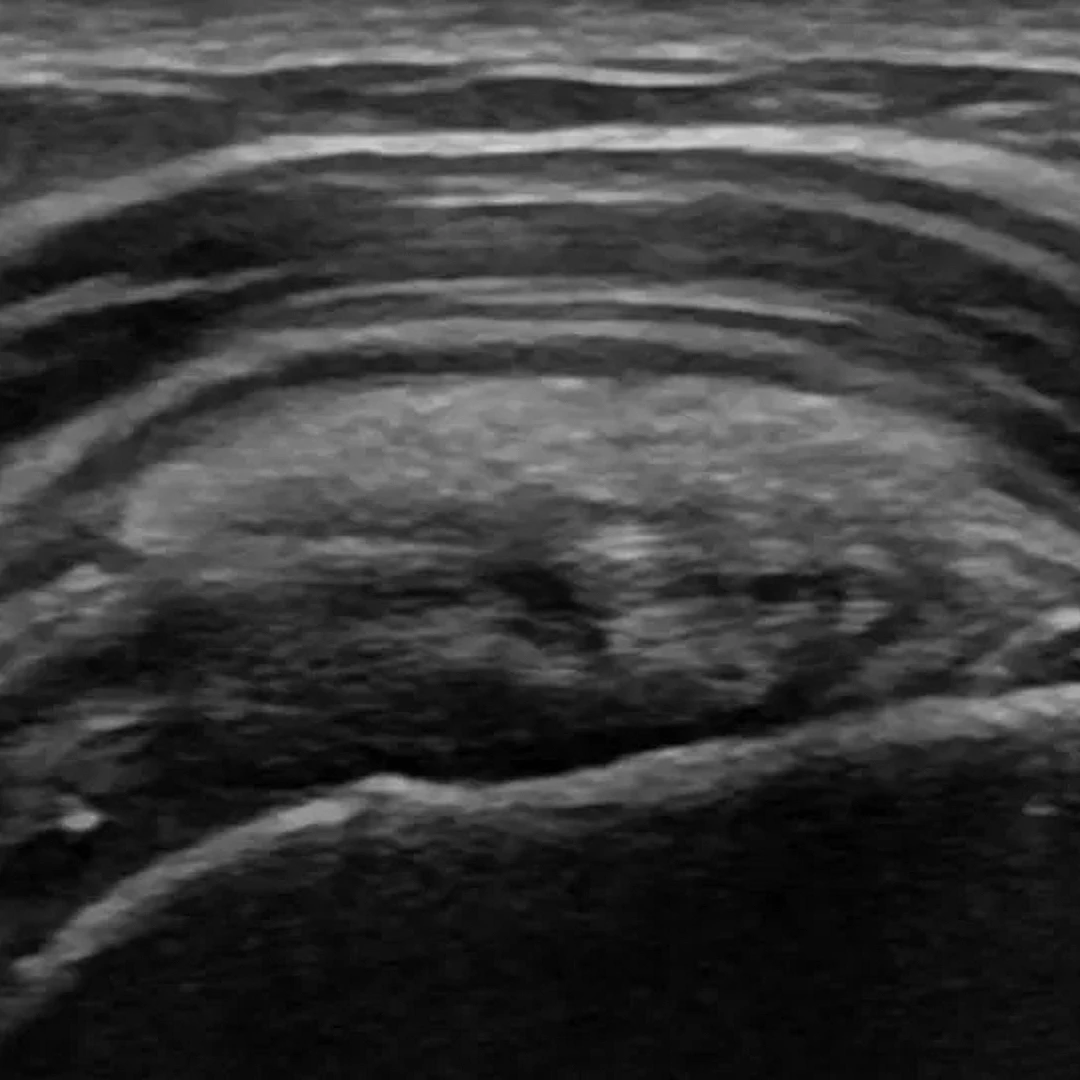

Scrotal Ultrasound

Scrotal Ultrasound provides detailed imaging of the testicles and surrounding tissues to detect lumps, pain, or swelling. It’s a non-invasive, radiation-free tool for evaluating male reproductive health.